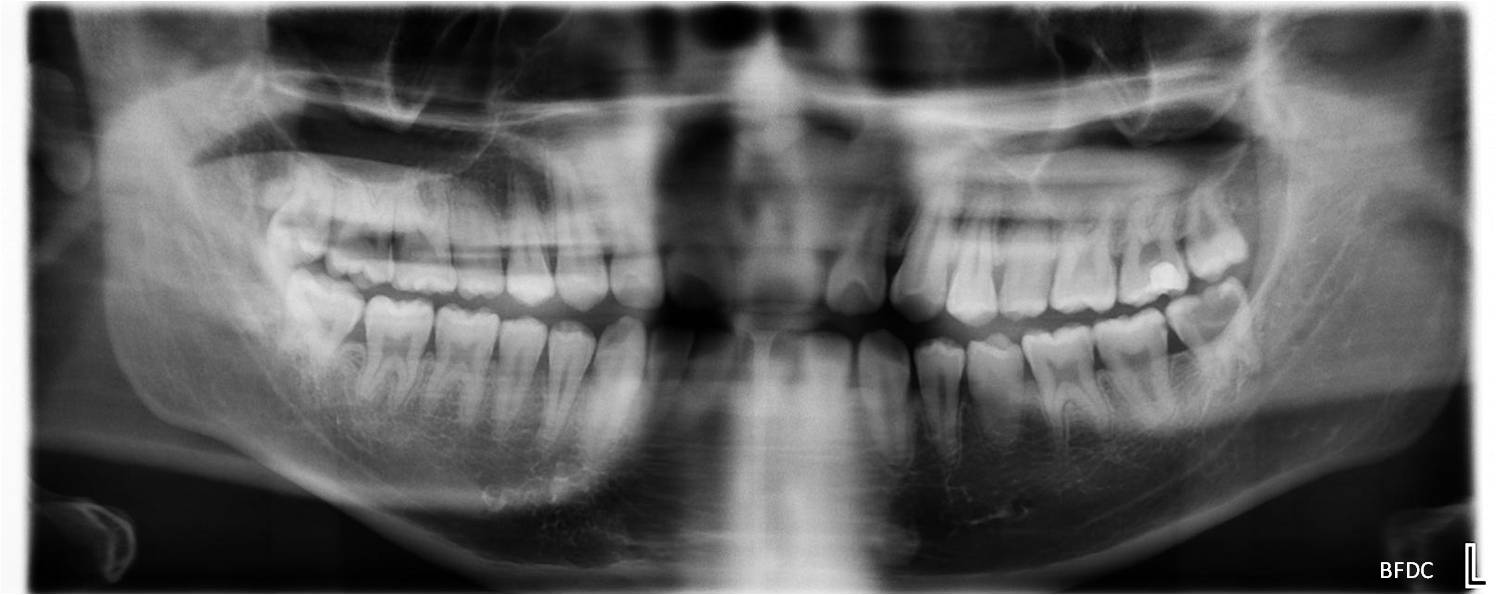

治療前,環口X光,深度蛀牙